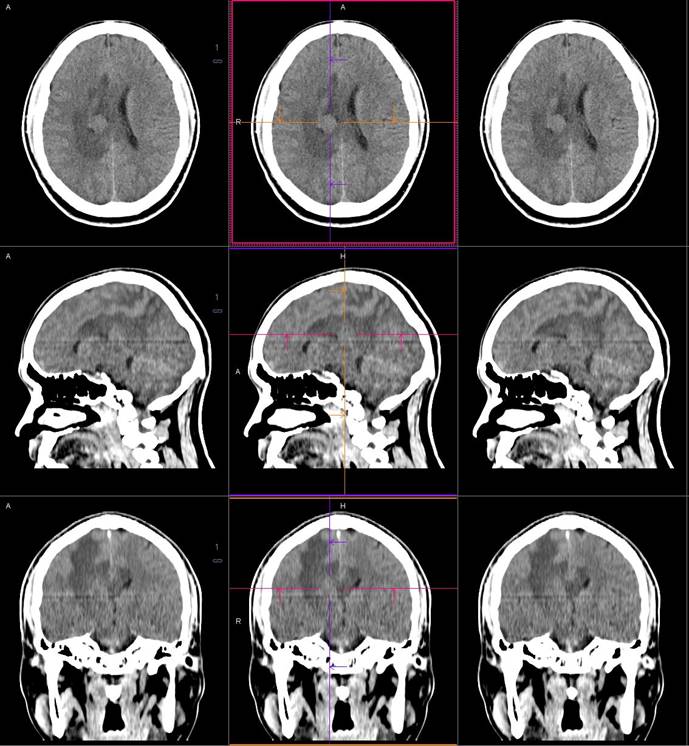

磁共振影像圖

圖1

圖2

圖3

圖4

MR診斷:右側(cè)側(cè)腦室三角區(qū)及側(cè)腦室旁占位,考慮惡性腫瘤可能,間變型腦膜瘤?轉(zhuǎn)移瘤?

CT鑒別診斷

CT是腦腫瘤的常用檢查方法,CT平掃及增強通過腫瘤的形態(tài)、密度及血供情況等對腦膜瘤的診斷和鑒別診斷有一定的價值。腦膜瘤為腦外腫瘤,但瘤周腦實質(zhì)水腫的出現(xiàn)率也較高,國外報道約60%。本例非典型腦膜瘤可見顯著的瘤周水腫。導致瘤周水腫的機制仍不明確,可能由多種因素參與、共同影響、相互制約所引起的一種血管源性水腫,腫瘤壓迫鄰近引流靜脈容易產(chǎn)生水腫,也有學者認為與腫瘤的血管內(nèi)皮生長因子、水通道蛋白-4高表達等因素有關。

MR鑒別診斷

常規(guī)MR檢查是診斷腦膜瘤的有效手段,可以明確腫瘤發(fā)生的部位、形態(tài)和數(shù)目等特征以及病變向鄰近腦實質(zhì)侵犯的程度和范圍,典型腦膜瘤呈等或(和)稍長T1、等或(和)稍長T2信號,??娠@示完整的包膜,增強掃描因腫瘤內(nèi)部新生血管通透性不同呈不同程度強化,由于腫瘤組織的強化程度與腫瘤的惡性程度不完全一致,導致MR常規(guī)檢查在腦膜瘤分級分型方面仍存在一定的困難。擴散加權成像( diffusion weighted imaging,DWI) 及表觀擴散系數(shù)( apparent diffusion coefficient,ADC) 被廣泛用于腦腫瘤的分級、分子分型和腫瘤侵襲性預測,并取得了良好的性能。目前,對于非典型腦膜瘤腦實質(zhì)侵犯的診斷的金標準依賴于組織病理學。